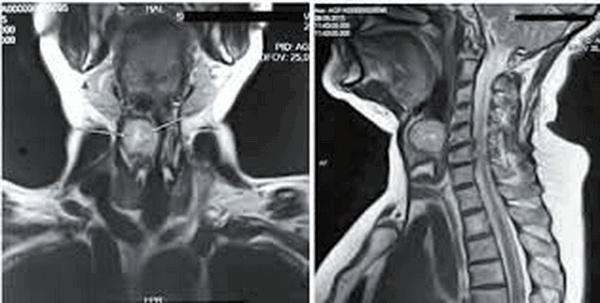

На фото МР-снимок органов лица, шеи и соответствующего отдела позвоночника

Патологии органов шеи могут проявляться незначительными симптомами или серьезно снижать качество жизни человека. Заболевания горла и гортани требуют точных методов диагностики, поскольку за периодической охриплостью голоса и другими признаками отклонений может стоять онкология. Чтобы получить достоверную информацию о происходящих в данной области процессах проводят магнитно-резонансную томографию. У пациента может возникнуть вопрос, что показывает МРТ горла и гортани. Метод отражает состояние мягких и костных тканей, нервной, сосудистой и лимфатической систем в шейном отделе позвоночника.

МР-снимок глотки и гортани